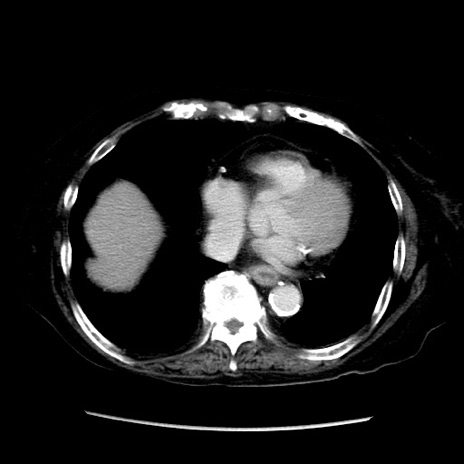

症例14(横断像)

【症例】 90歳代女性

【主訴】 腹痛・嘔吐

【現病歴】今朝から左側腹部痛を認めた。 経過観察していたが、嘔吐を認めたため来院。

【既往歴】 子宮癌術後

【身体所見】 意識清明、BP 127/54mmHg、P 98bpm Sp02 95%(RA)、BT 35.8°C、腹部平坦・軟腸ぜん動音聴取良好、右下腹部圧痛(+) 反跳痛なし

【データ】WBC 9800、CRP 0.46